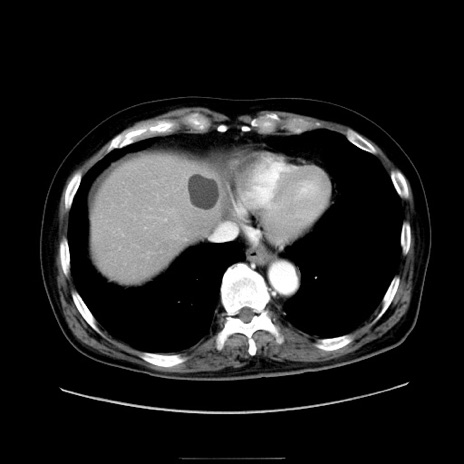

症例30(横断像)

冠状断像

【症例】80歳代男性

【現病歴】約6時間前から臍下部痛が出現。次第に腹部膨隆・背部痛も生じてきたため来院。背部痛の場所は変化しない。

【身体所見】意識清明、BT 36.3℃、BP  131/87mmHg、P 87bpm、SpO2 100%(RA)、臍周囲自発痛・圧痛あり、反跳痛なし、自発痛部位に一致して板状硬あり、腹部膨隆、腸雑音減弱、CVA tenderness両側陰性。